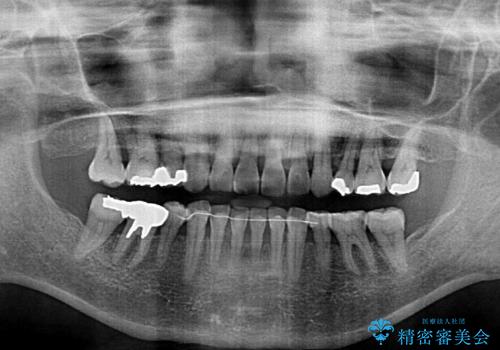

- 2年7ヶ月

- 突出した口元を引っ込めることを希望して来院された患者様です。

上下左右第一小臼歯4本を抜歯して、口元を改善するワイヤー矯正を行うこととしました。

長年気にされていた口元の突出感が改善されたため、もっと若い時分に矯正をすればよかったと思われていました。